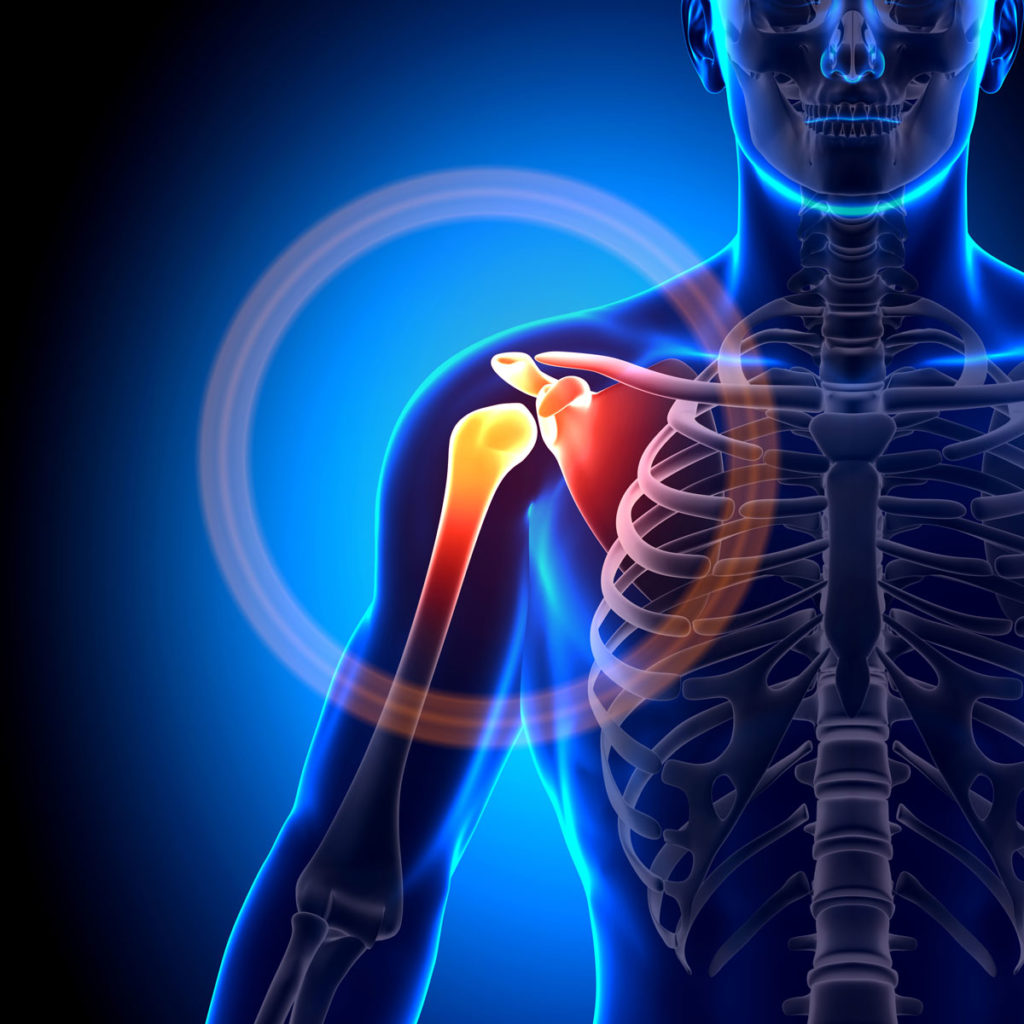

The joint system is a complex that allows bones to be linked together to allow proper movement of the body.It is therefore necessary to take care of it.The body is made up of several joints, however, there is one that requires greater attention than the others because it is often subject to injury: the shoulder.

The joint at the shoulder is defined as a joint complex because in order to function properly, 5 joints come into play.The synergy of these 5 elements ensures various arm movements.Very wide conical movements, arm lifts and circular movements are possible with a good shoulder.

- the Glenohumeral links the trunk to the upper limb and unites the humeral head to the glenoid cavity of the scapula.

- the Subdeltoid: connection between the humeral head and the acromion of the scapula

Because of this composition, which is not lesser, the articular system of the shoulder is very complex, fragile and unstable.This is why taking care of it is essential.

In the glenohumeral joint, instability is very present.This is due to the size of the head of the humerus in relation to the glenoid cavity.Indeed, to ensure arm movements, these two bones must come into contact and the arm bone must even slide over the socket.Thus, in order to guarantee the movement of the humerus while ensuring the alignment of its head, the muscles which play the role of adjusters must intervene.Several muscles in the form of tentacles cover the humeral head to maintain contact with the glenoid cavity: this is the cuff.